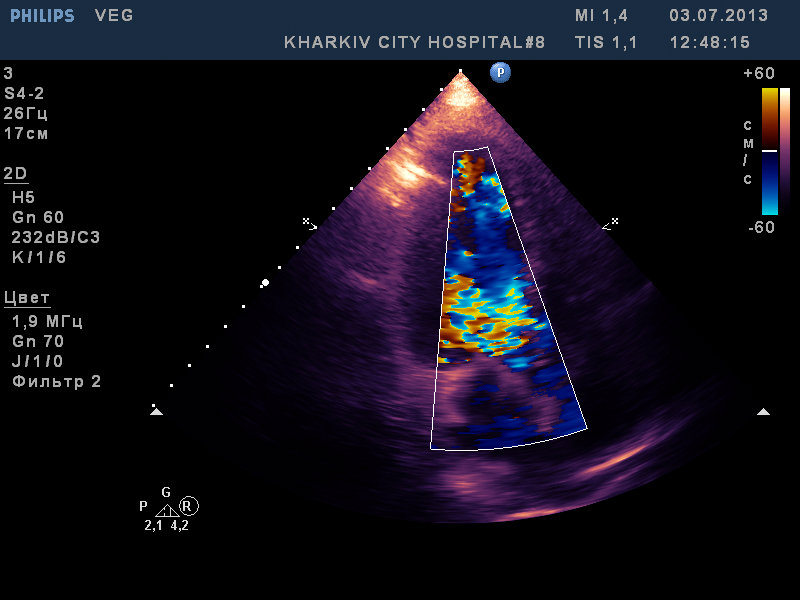

вегетации на АК, МК и ТК

:shock: вегетации на АК, МК и ТК,дилатация полостей, выраженная недостаточность клапанов.

молодой 37лет, с гепатитом C, возможно имеет место быть ВИЧ. по виду наркоман с конкретным стажем